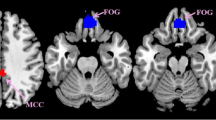

VMHC was significantly decreased in the CSA group compared to NCs in four regions: bilateral cerebellum, bilateral frontal sup orb, bilateral temporal inf, and bilateral frontal sup (Fig. 1, Table 2). The mean VMHC values are represented in (Fig. 1c). In the CSA group, there was no association between clinical features and average VMHC values in different brain regions (all P > 0.05).

Interhemispheric connectivity in the CSA versus NCs. Significant differences were observed in the RC, LC, RFSO, LFSO, RTI and LTI. (a): The lower VMHC values was indicated by yellow areas showed P < 0.01 for multiple comparisons analyze within GRF theory, P < 0.01, z > 2.3, cluster above 40 voxels with corrected FWE; (b): The mean VMHC values were altered between the CSA and NCs, P < 0.01 for multiple comparisons using GRF theory (z > 2.3, P < 0.01, cluster > 40 voxels); (c): The differences observed in the interhemispheric connectivity were significant in the RC, LC, RFSO, LFSO, RTI and LTI. RC right cerebellum, LC left cerebellum, RFSO right frontal sup orb, LFSO left frontal sup orb, RTI right temporal inf, LTI left temporal inf, RFS right frontal sup, LFS left frontal sup.